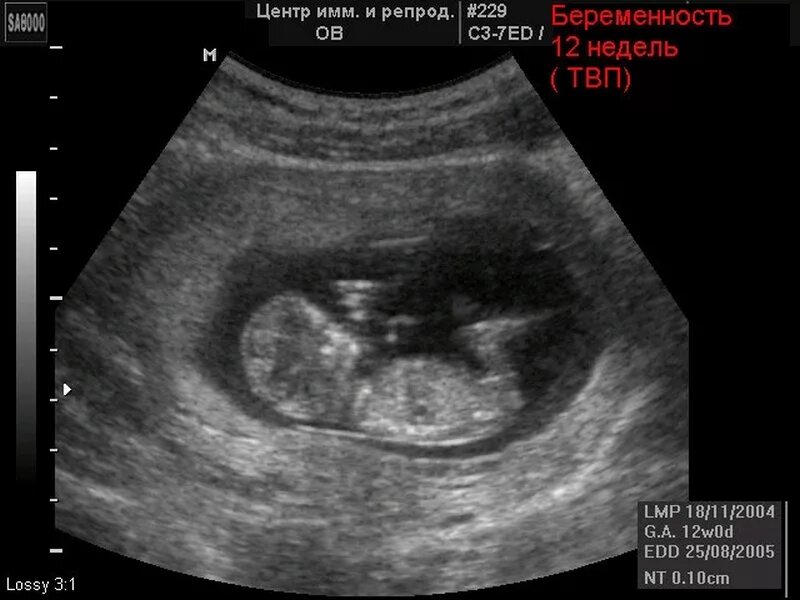

Большой плод при беременности